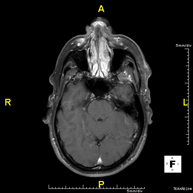

- RM Cerebral (cranial)

Prova diagnòstica no invasiva que consisteix en l'obtenció d'imatges d'alta definició anatòmica del cerbell mitjançant l'ús d'un camp electromagnètic i ones de ràdio (com un emissor i un receptor). No utilitza radiació ionitzant. Indicacions: problemes vasculars, pèrdua de memòria, epilèpsia, cefalea, malformacions, sospita de tumor, meningitis. - RM de Cais